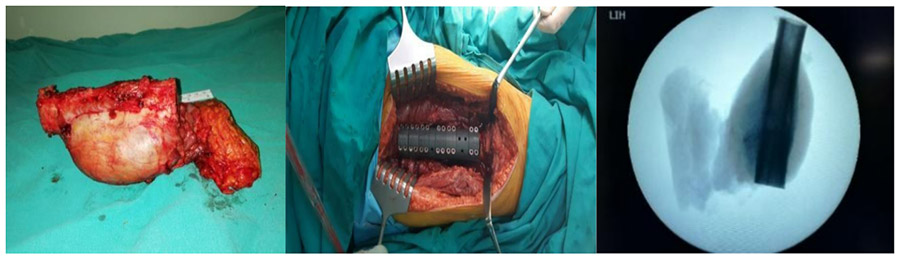

During the operation: The macroscopic and fluoroscopy images of the removed tumor are shown, along with the implanted tumor prosthesis.